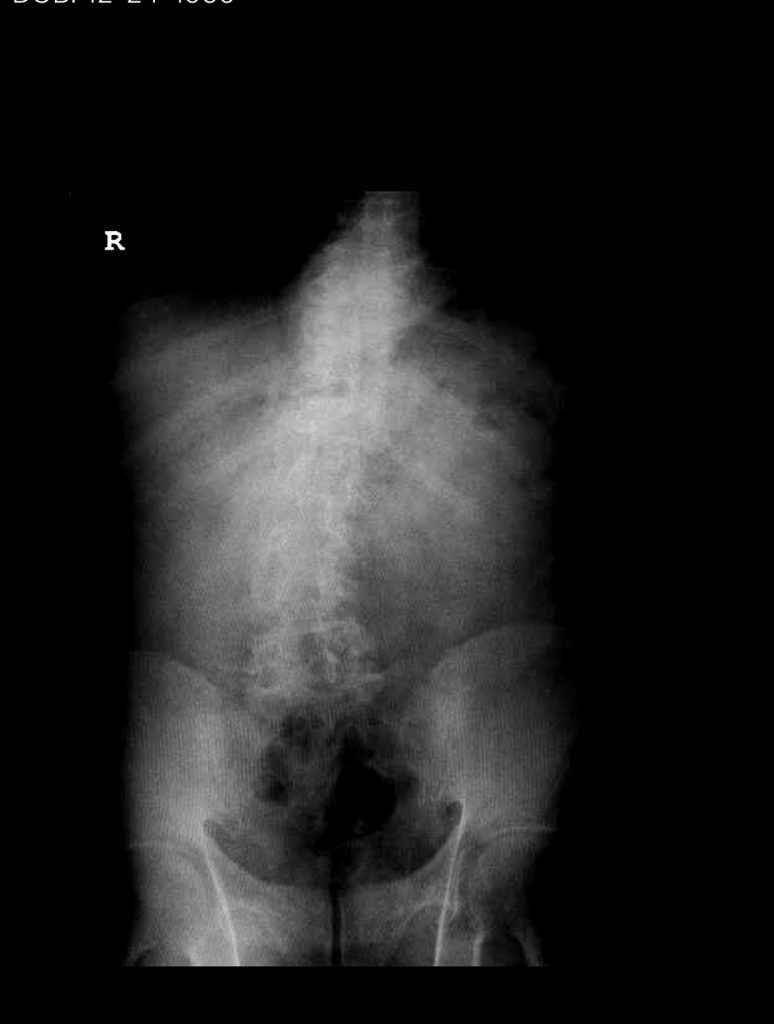

Figure 2. T2-weighted sagittal and axial MRIs demonstrating severe L3-4 stenosis and an L5-S1 grade 1 spondylolisthesis and spondylolysis and L3-4 retrolisthesis. Note the anterior osteophyte formation at L2-3 with attempted autostabilization of segment.

He had mild proximal weakness of his hip flexors. He also had a history of diabetes, hypertension, and hypercholesterolemia. Imaging studies were obtained. Plain x-rays (Fig. 1) demonstrated a degenerative levoscoliosis with the apex of the curve at L2-3. Lumbar MRI (Fig. 2) showed severe degenerative disc disease with an L5-S1 grade 1 spondylolisthesis and a significant retrolisthesis at L3-4 with severe lumbar stenosis.